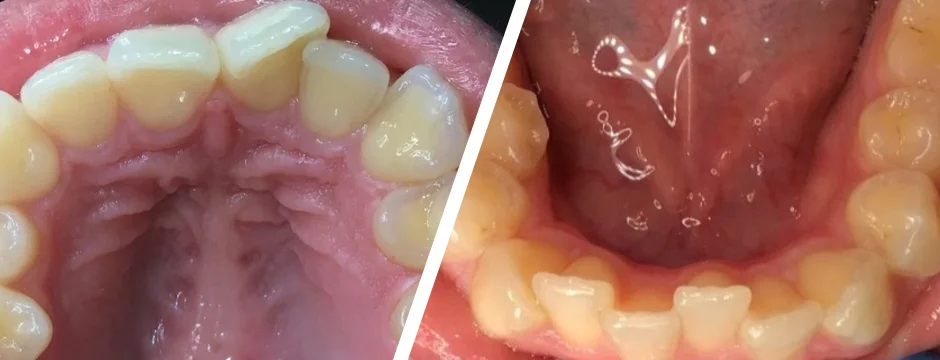

Lower Anterior Veneers

Lower Anterior Veneers<br />

Upper Anterior Veneers